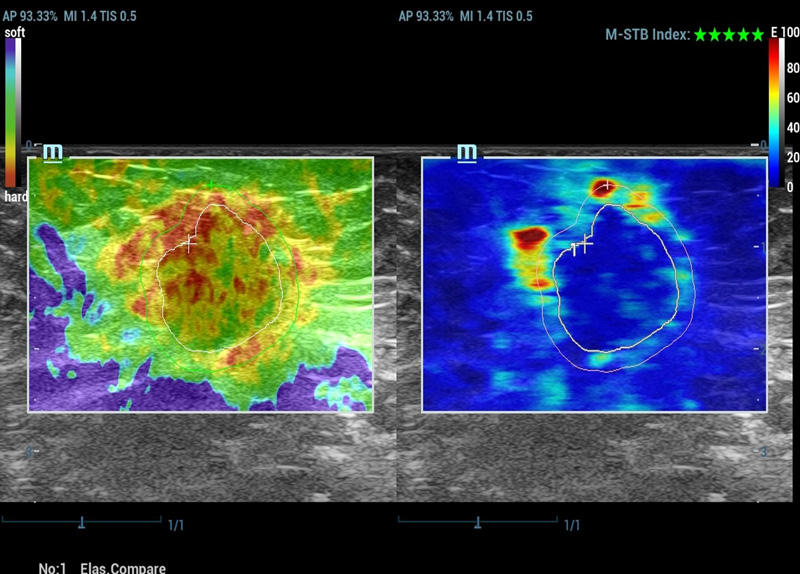

M-Reference E Compare

Strain e Shear wave juntos inspiram o futuro

M-Reference C&E

CEUS e Shear wave juntos desvendam o mundo do ultrassom multiparamûˋtrico

Ferramentas de anûÀlise multiparamûˋtrica M-Reference

M-Ref. E Compare

M-Ref. E Compare ã Tumor maligno de mama

M-Ref. E Compare oferece suporte û exibi??o tanto da elastografia por deforma??o em tempo real quanto da STE em um û¤nico plano para avalia??o da rigidez do tecido.